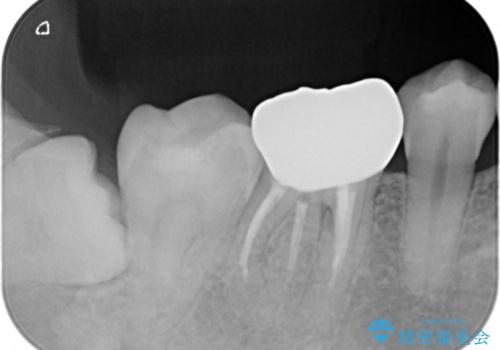

被せ物の下で進行してしまった虫歯の治療

- 歯が欠けてしまったと来院された方です。

メタルインレーが一部欠けており、その下には大きな虫歯ができていました。

再精密根管治療もご提案しましたがご希望されなかったため、今回は土台と被せ物のみ治療介入しました。